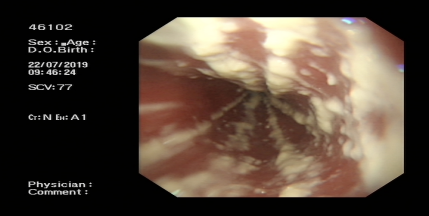

Ⅳ、ESTD治疗多灶性复发型食管早癌

Ⅴ、ESTD治疗超低位大面积直肠早癌